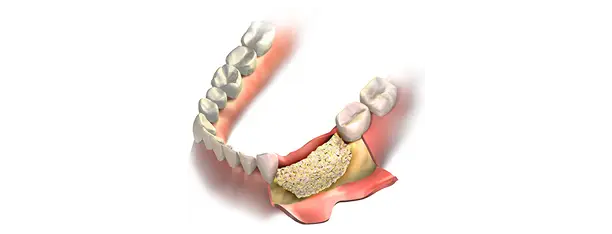

Adiția osoasă

Reface volumul osos pierdut din diverse cauze, precum afecțiuni parodontale sau lipsa dinților. Această intervenție pregătește terenul pentru inserarea implanturilor dentare prin utilizarea de materiale biocompatibile sau os prelevat de la pacient. Astfel, procesul de vindecare este optimizat, iar riscul de complicații este minimizat.